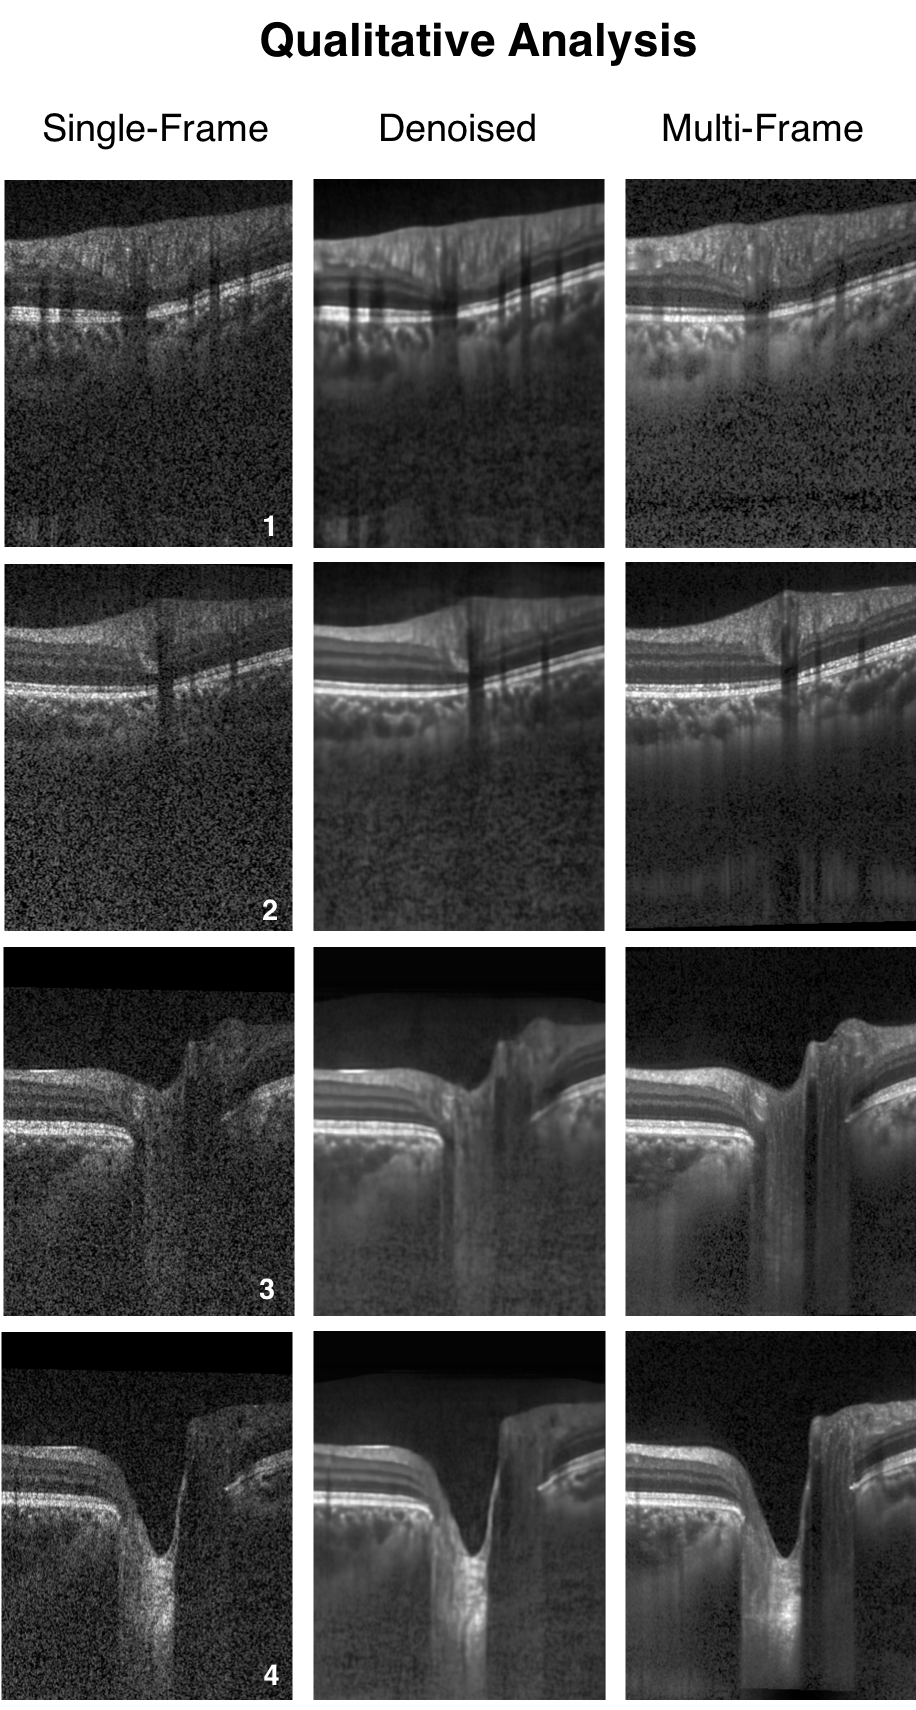

When trained with the ‘clean’ B-scans (multi-frame) and the corresponding ‘noisy’ B-scans, our network was able to successfully denoise unseen single-frame B-scans. The single-frame, denoised and multi-frame B-scan for a healthy subject can be found in (Figure 3). In all the cases, the denoised B-scans were qualitatively similar to their corresponding multi-frame B-scans (Figure 4). Overall, the visibility of all ONH tissues were prominently enhanced (Figure 3; B).

Using the proposed network, we obtained denoised B-scans that were qualitatively similar to their corresponding multi-frame B-scans (Figure 3) and (Figure 4), owing to the reduction in noise levels. The mean SNR for the denoised B-scans was dB, a two-fold improvement (reduction in noise level) from improvement from dB that was obtained for the single-frame B-scans, thus offering an enhanced visibility of the ONH tissues. Given the significance of the neural (retinal layers) [79, 80, 81, 82, 83] and connective tissues (sclera and LC) [84, 85, 86, 87, 88], in ocular pathologies such as glaucoma [2], and age-related macular degeneration [89], their enhanced visibility is critical in a clinical setting. Furthermore, reduced noise levels would likely increase the robustness of aligning/registration algorithms used to monitor structural changes over time [18]. This is crucial for the management of multiple ocular pathologies [90, 91].